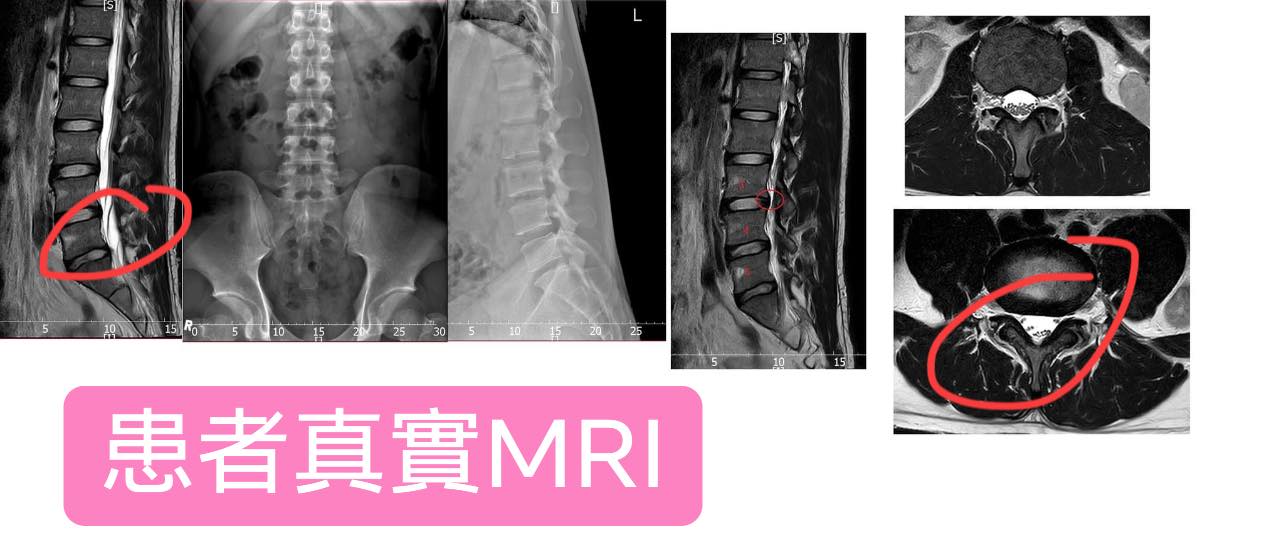

✳️診斷:梨狀肌症候群同時合併椎間盤突出